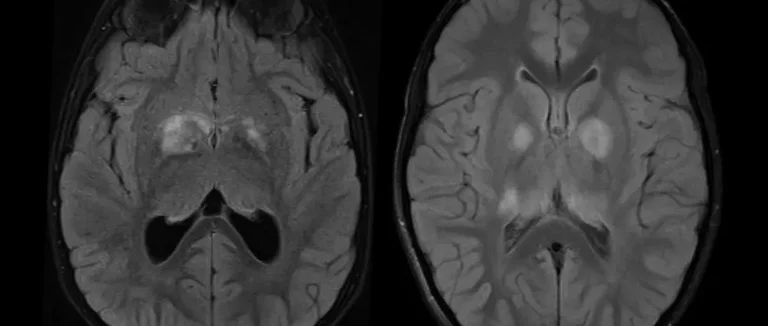

Examens d'Imagerie Médicale

Les examens d'imagerie médicale sont essentiels pour diagnostiquer les tumeurs cérébrales bénignes. L'imagerie par résonance magnétique (IRM) et la tomodensitométrie (TDM) sont les plus utilisées.

L'IRM donne des images détaillées du cerveau. Cela permet de voir la taille, la forme et l'emplacement de la tumeur. La TDM aide à détecter les calcifications et les changements osseux liés à certaines tumeurs.